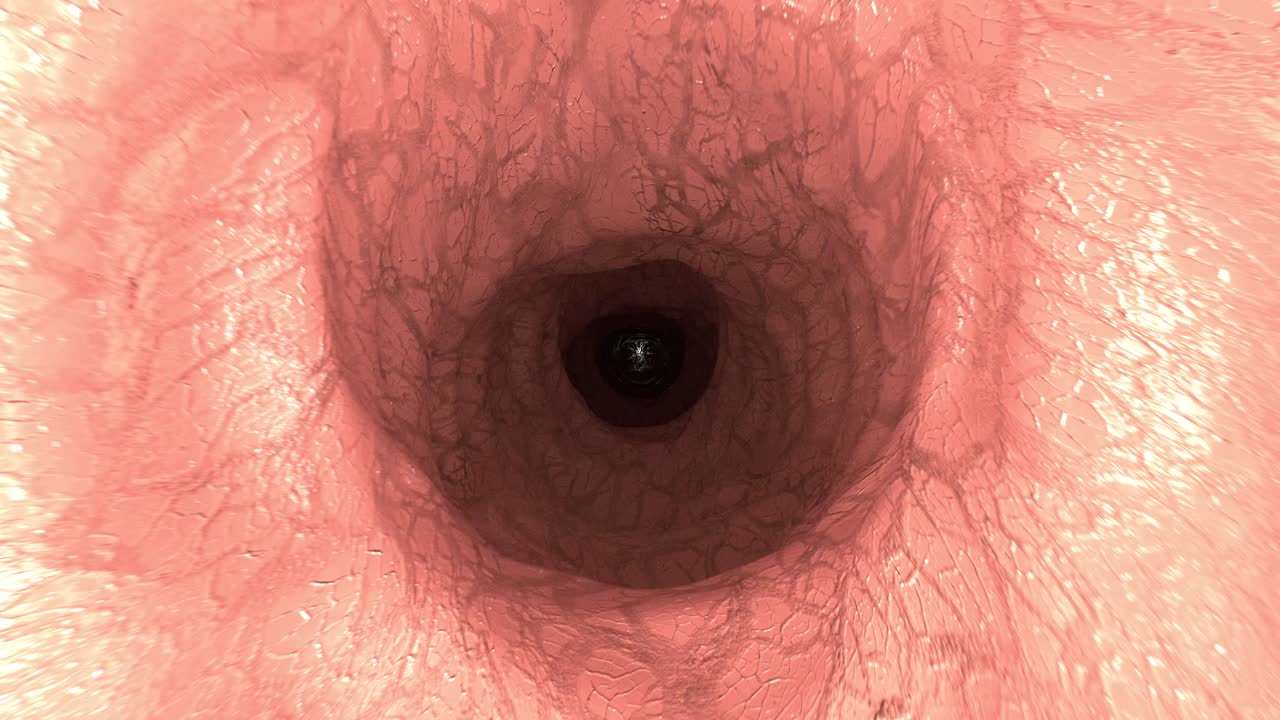

endoscopio cámara médica intestino colon médico endoscopia cirugía 4k